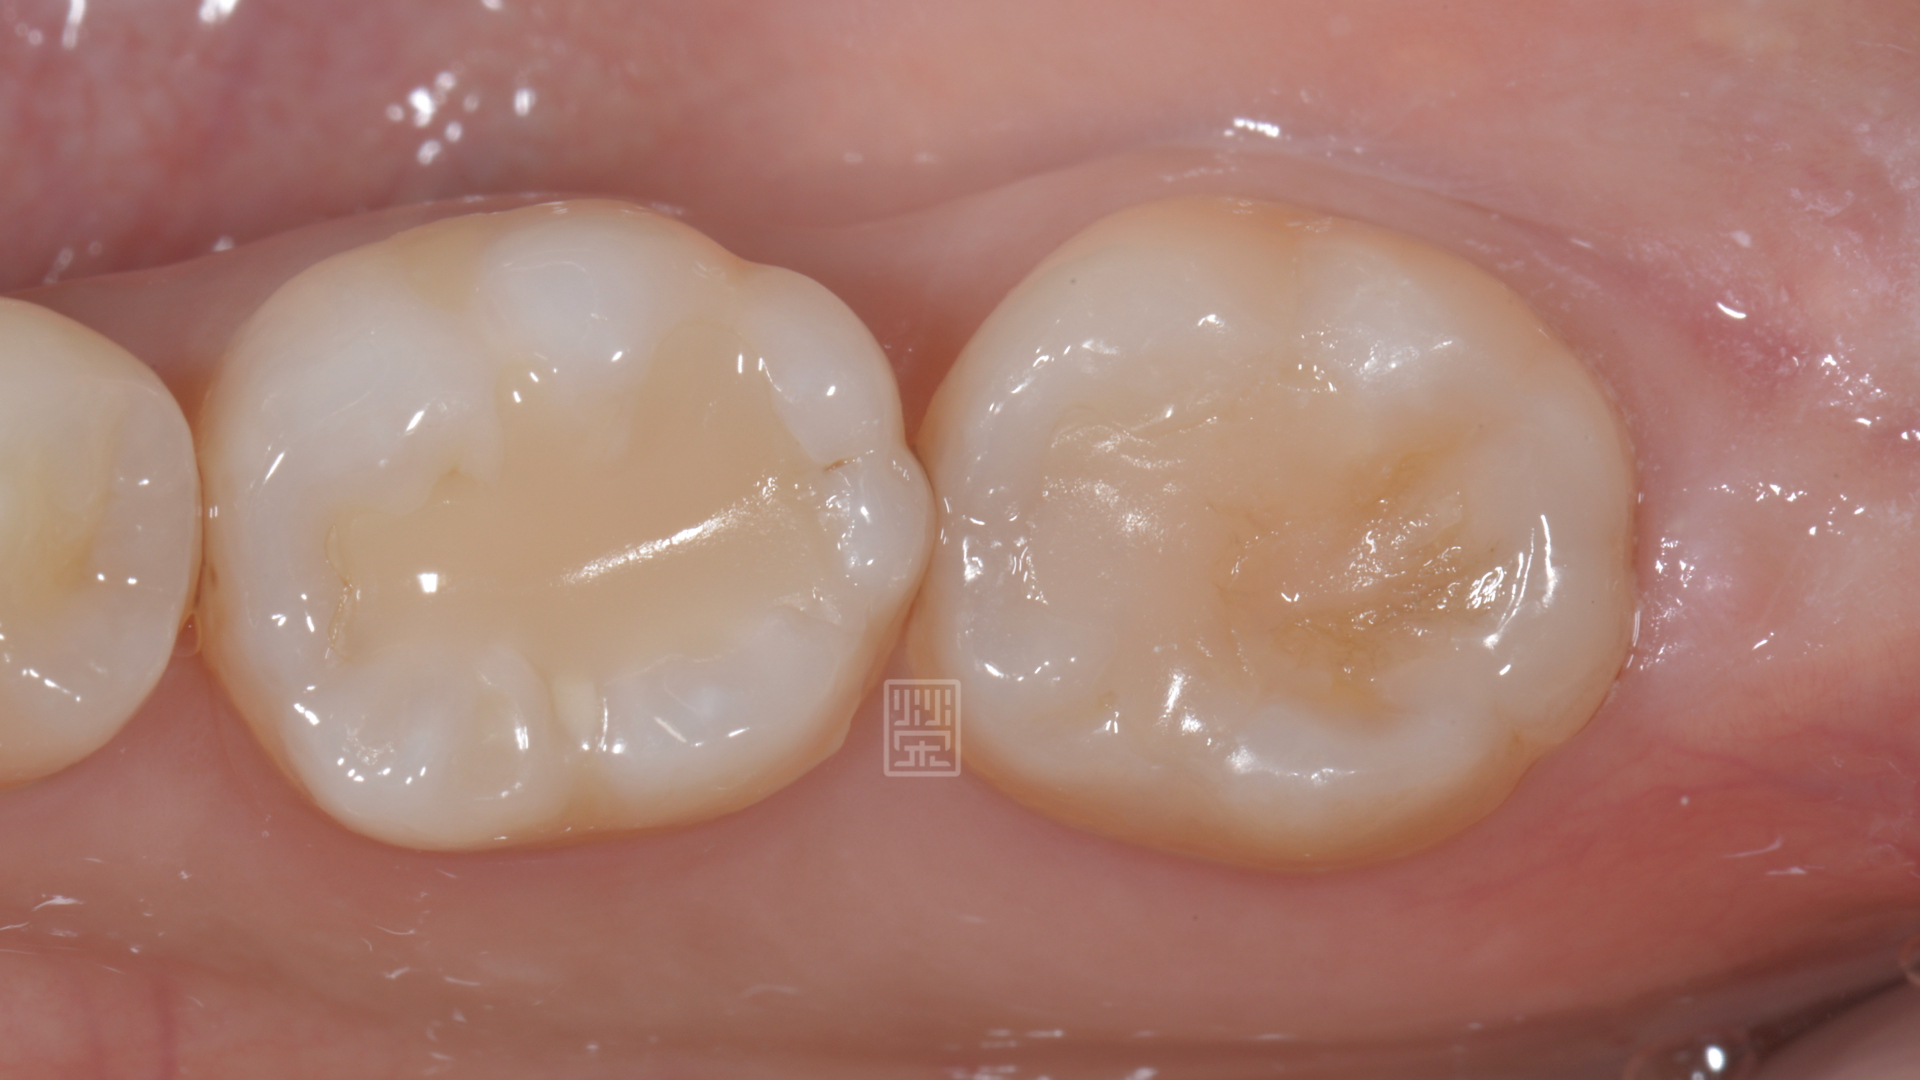

染色劑發現牙齒有裂痕